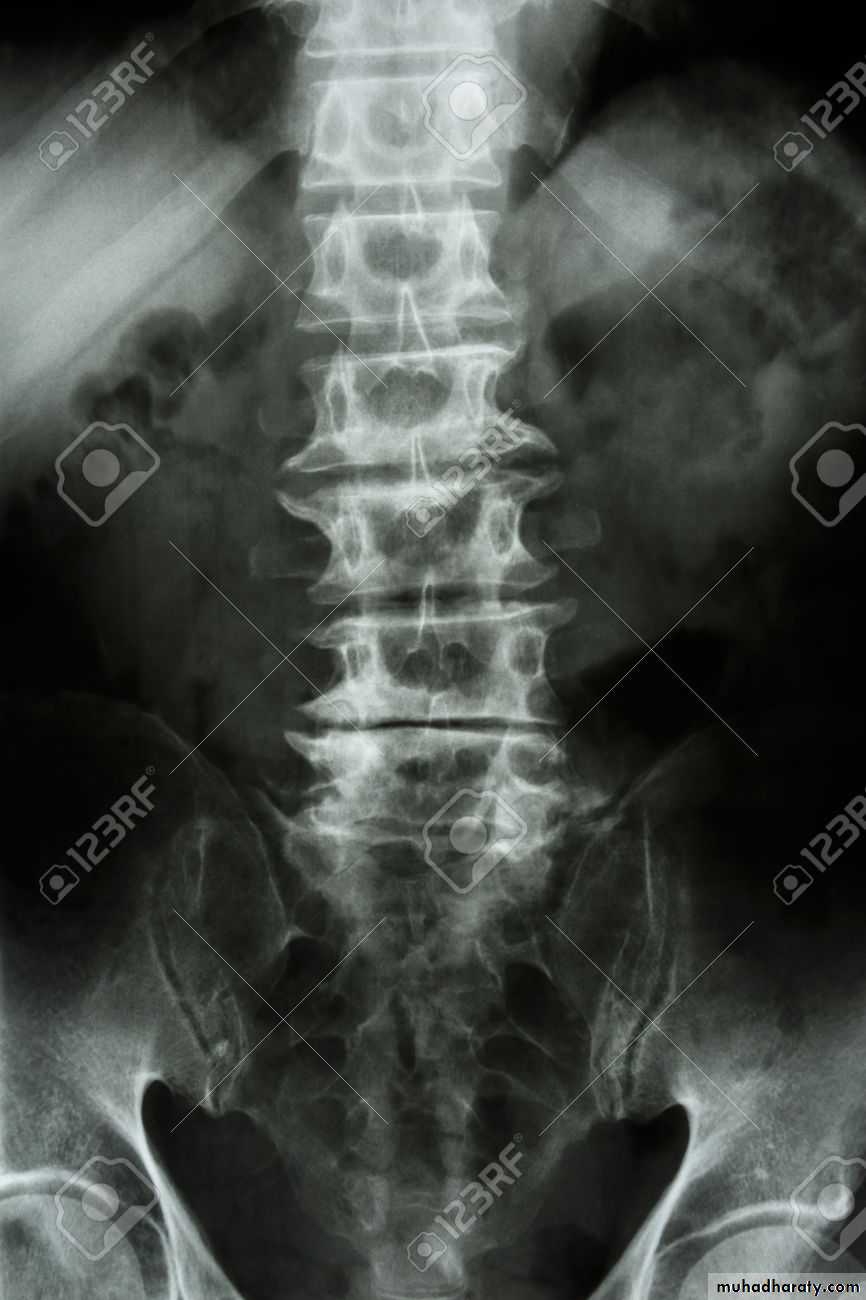

In the Spine :

* Lower cervical and low lumbar spine are most comonly affected.* Osteophytes may encroach on neural foramina (best seen on oblique views).

*Vacuum phenomenon: gas (N2),is pathognomonic of the degenerative process.

* OA of the spine occurs in the apophyseal joints .

* Degenerative spondylolisthesis (pseudospondylolithesis)

Lumbar spondylosis. There is distal narrowing and a vacuum

phenomenon is present in the degenerative discs. Marginal osteophytes arepresent. Inferiorly the facet joints show features of degeneration and, with the increase in lordosis, the spinous processes are in contact